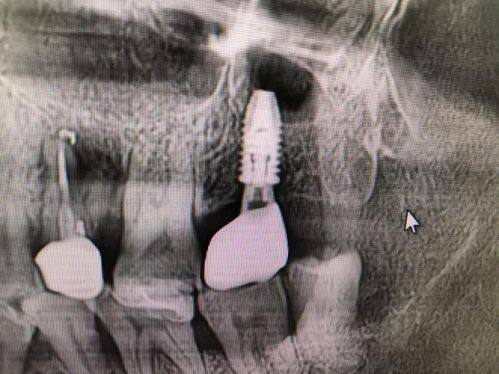

种植牙:包含普通种植、即刻种植、微创种植牙等技术,种植医生具备口腔修复学硕士学位,可针对部分牙列缺损、全口牙列缺损制定个性化种植方案,兼顾种植牙的稳定性与美观性,术后成效获患者认可。

祝小鹏:主治医师,口腔修复学硕士,擅长普通种植、即刻种植、微创种植牙及美学修复,专注解决部分牙列缺损和全口牙列缺损问题,能制定个性化种植方案,兼顾修复的功能性与美观性。